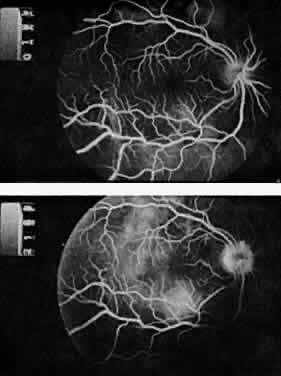

The classic ocular finding in DIC is serous retinal detachment64,65 (Fig. 5). The pathogenesis of these detachments involves choriocapillaris occlusion resulting in retinal pigment epithelial damage and subsequent loss of retinal pigment epithelial barrier and pump function. Fluorescein angiography confirms this pathophysiology, showing delayed filling of the posterior choroid with later pigment epithelial staining (Fig. 6). If the underlying DIC can be reversed, the retina may reattach, with return of vision. Other findings associated with DIC include retinal and vitreous hemorrhages.

Fig. 6. Delayed choroidal filling with pigment epithelial staining in disseminated intravascular coagulation. (Hoines J, Buettner H: Ocular complications of disseminated intravascular coagulation [DIC] in abruptio placentae. Retina 9:107, 1989.)

The most common ocular manifestations of TTP include papilledema, extraocular muscle palsies, and visual field defects, which usually are secondary to concomitant CNS involvement.75 Retinal findings consist of hemorrhages, retinal vascular occlusions, and serous detachments76,77 (Figs. 8 to 10). The cause of the serous detachments appears to be focal occlusion of the choriocapillaris resulting in retinal pigment epithelial damage and blood-retinal barrier disruption.76,77 Findings on fluorescein angiography are characterized by focal areas of nonperfusion of the choriocapillaris associated with late leakage into the subretinal space76 (Fig. 11). This is consistent with histopathologic studies that show occlusion of the choriocapillaris and large choroidal vessels, presumably by fibrin, with overlying necrosis of thepigment epithelium.75,76 TTP also has been linked in one case report with Purtscher retinopathy.78

Fig. 9. Fluorescein angiogram of patient with thrombotic thrombocytopenic purpura and vascular-occlusive disease. (Courtesy of William Mieler, MD.)

Fig. 11. Fluorescein angiogram of patient with thrombotic thrombocyto-penic purpura showing late choroidalhyperfluorescence caused by focal areas of choriocapillaris nonperfusion. (Courtesy of Jerry Neuwirth, MD.)